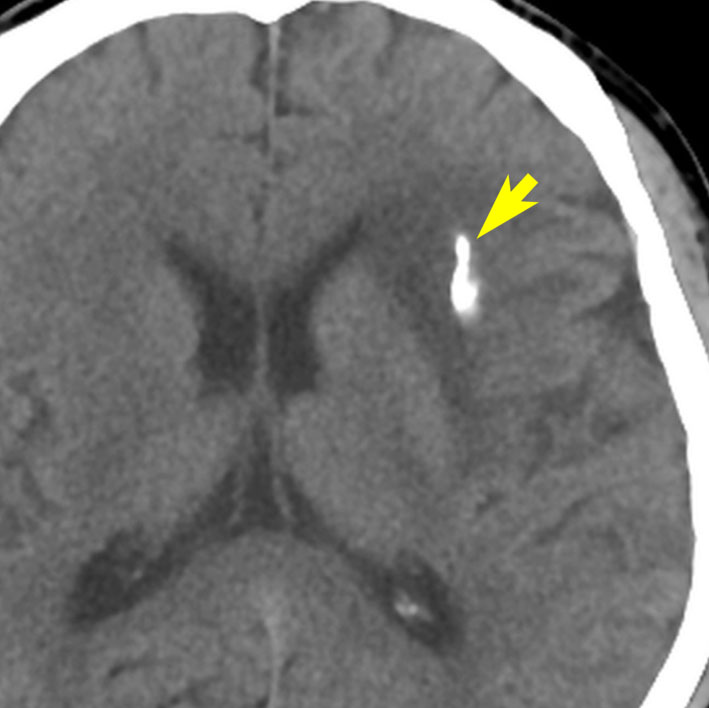

診断 CT

• 診断のためにはCTとMRIが必須です

• CTでは,石灰化やのう胞を伴う境界不鮮明な低吸収域(黒っぽく見える)として捉えられます

• 特に石灰化は星細胞系腫瘍との鑑別診断に非常に重要な所見です

• 脳石 brain stoneといわれる岩のような大きな塊の石灰化もあります

CTで白く見えるのが石灰化です。周りの少し黒っぽいところは乏突起膠腫です。CTでは腫瘍の全体像は見れませんからMRIが必要です。